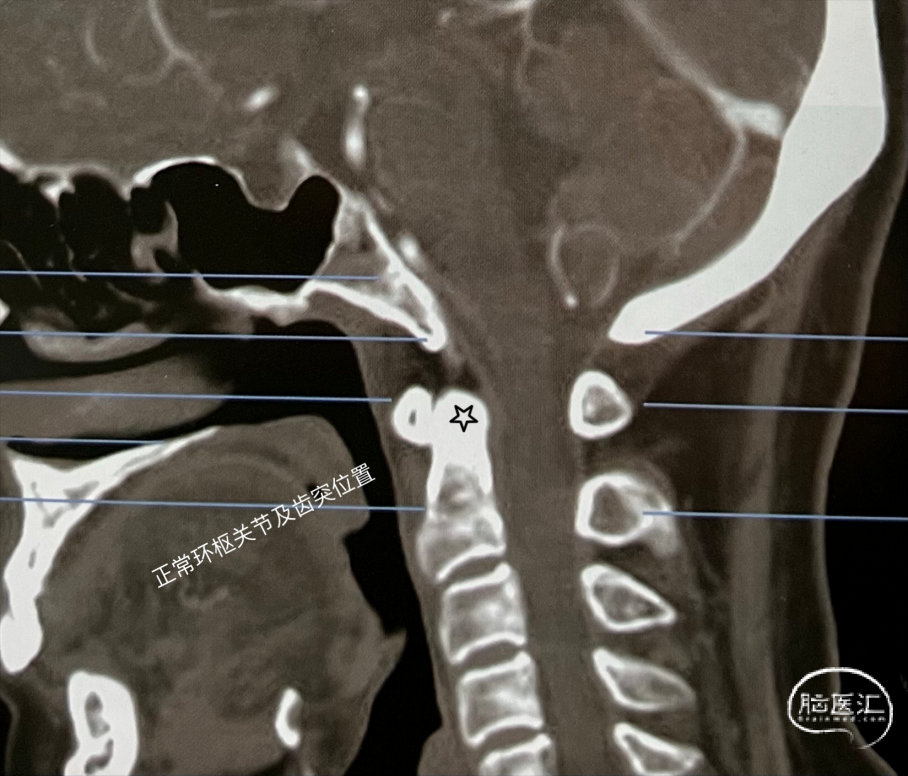

颅底凹陷症(basilarinvagination)的主要发病原因为先天性⻣质发育不良所致,由于在胚胎发⽣学上神经管在寰枕部闭合最晚所以先天性畸形容易发⽣在此区。少数可继发于其他疾病。本病分为2型:① 先天型:⼜称原发性颅底凹陷症,伴有寰枕融合、枕⻣变扁、枕⻣⼤孔变形、⻮状突向上移位甚⾄进 ⼊枕⻣⼤孔内,致使枕⻣⼤孔前后径缩⼩。在胚胎发育2~3周时由于胚胎分节的局部缺陷,寰椎不同程度地进⼊枕⻣⼤孔内有时与之融合等。近年来有⼈发现本病与遗传因素有关,即同⼀家族兄弟姐妹中可有数⼈发病。②继发型:⼜称获得型颅底凹陷症,较少⻅常继发于⻣炎、成⻣不全佝偻病⻣软化症、类⻛湿性关节炎或甲状旁腺功能亢进等导致颅底⻣质变软,变软的颅底⻣质受到颈椎压迫⽽内陷枕⼤孔升⾼,有时可达岩⻣尖,且变为漏⽃状。同时颈椎也套⼊颅底,为了适应寰椎后⼸,在枕⼤孔后⽅可能出现隐窝,⽽寰椎后⼸并不与枕⻣相融合。颅底凹陷症导致枕⻣⼤孔狭窄,后颅窝变⼩,压迫延髓、⼩脑及牵拉神经根产⽣⼀系列症状,合并有椎动脉受压出现供⾎不⾜表现。晚期常出现脑脊液循环障碍⽽导致梗阻性脑积⽔和颅内压增⾼。颅底凹陷常合并脑脊髓和其他软组织畸形,如⼩脑扁桃体疝、脊髓空洞症及蛛⽹膜粘连等。呼吸肌功能衰减常常使患者感觉⽓短,说话⽆⼒,严重者可能出现不同程度的中枢性呼吸抑制,睡眠性呼吸困难等。